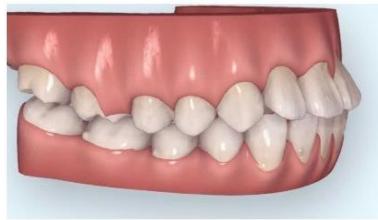

Intraoral examination revealed severe proclination and protrusion of both the maxillary and mandibular incisors [6]. The occlusal relationship was Class I at the canine (tooth 3) and first molar (tooth 6) levels bilaterally. A critical unfavorable biological factor was the proximity of the mandibular incisor roots to the labial cortical plate, representing a high-risk condition when planning extraction-based anterior retraction mechanics [10-12]. All four third molars were present.

Figure 2: Pre-Treatment Intraoral Photographs

Figure 3: Pre-Treatment Intraoral 3D Digital Models